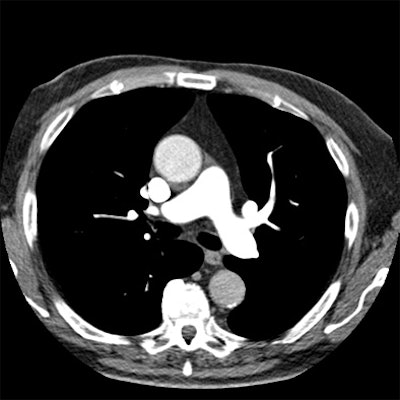

| Axial images of the thorax above and below were created from a pulmonary embolism study acquired in 0.2 seconds at dual-source CT in Flash mode, using the P3T algorithm to create the contrast injection protocol. The pulmonary and segmental arteries are well-enhanced (> 300 HU), with adequate enhancement in the aorta. The contrast protocol was created based on the patient's weight, scan duration, contrast concentration, and time to peak of a 15-mL timing bolus. This patient received 68 mL of 370 mgI/mL contrast at 5.2 mL per second. (A mixture phase of 35 mL, 20% contrast, was followed by a saline flush of 40 mL, all at the same flow rate.) Images courtesy of J. Michael Barraza. |